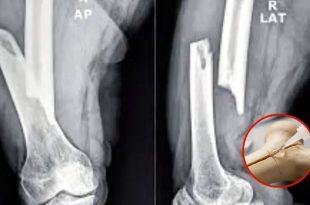

মাত্র তিন মিনিটে ভাঙা হাড় জোড়া লাগানোর মতো এক চমকপ্রদ চিকিৎসা প্রযুক্তি উদ্ভাবনের দাবি করেছেন চীনা গবেষকরা। ‘বোন-০২’ নামের এই বিশেষ ধরনের হাড়ের আঠা শুধু হাড়ের ভাঙাই সারাবে না, ভাঙা অংশে যন্ত্রপাতি বসাতেও সহায়তা করবে। চীনের ঝেজিয়াং প্রদেশের এক গবেষক …